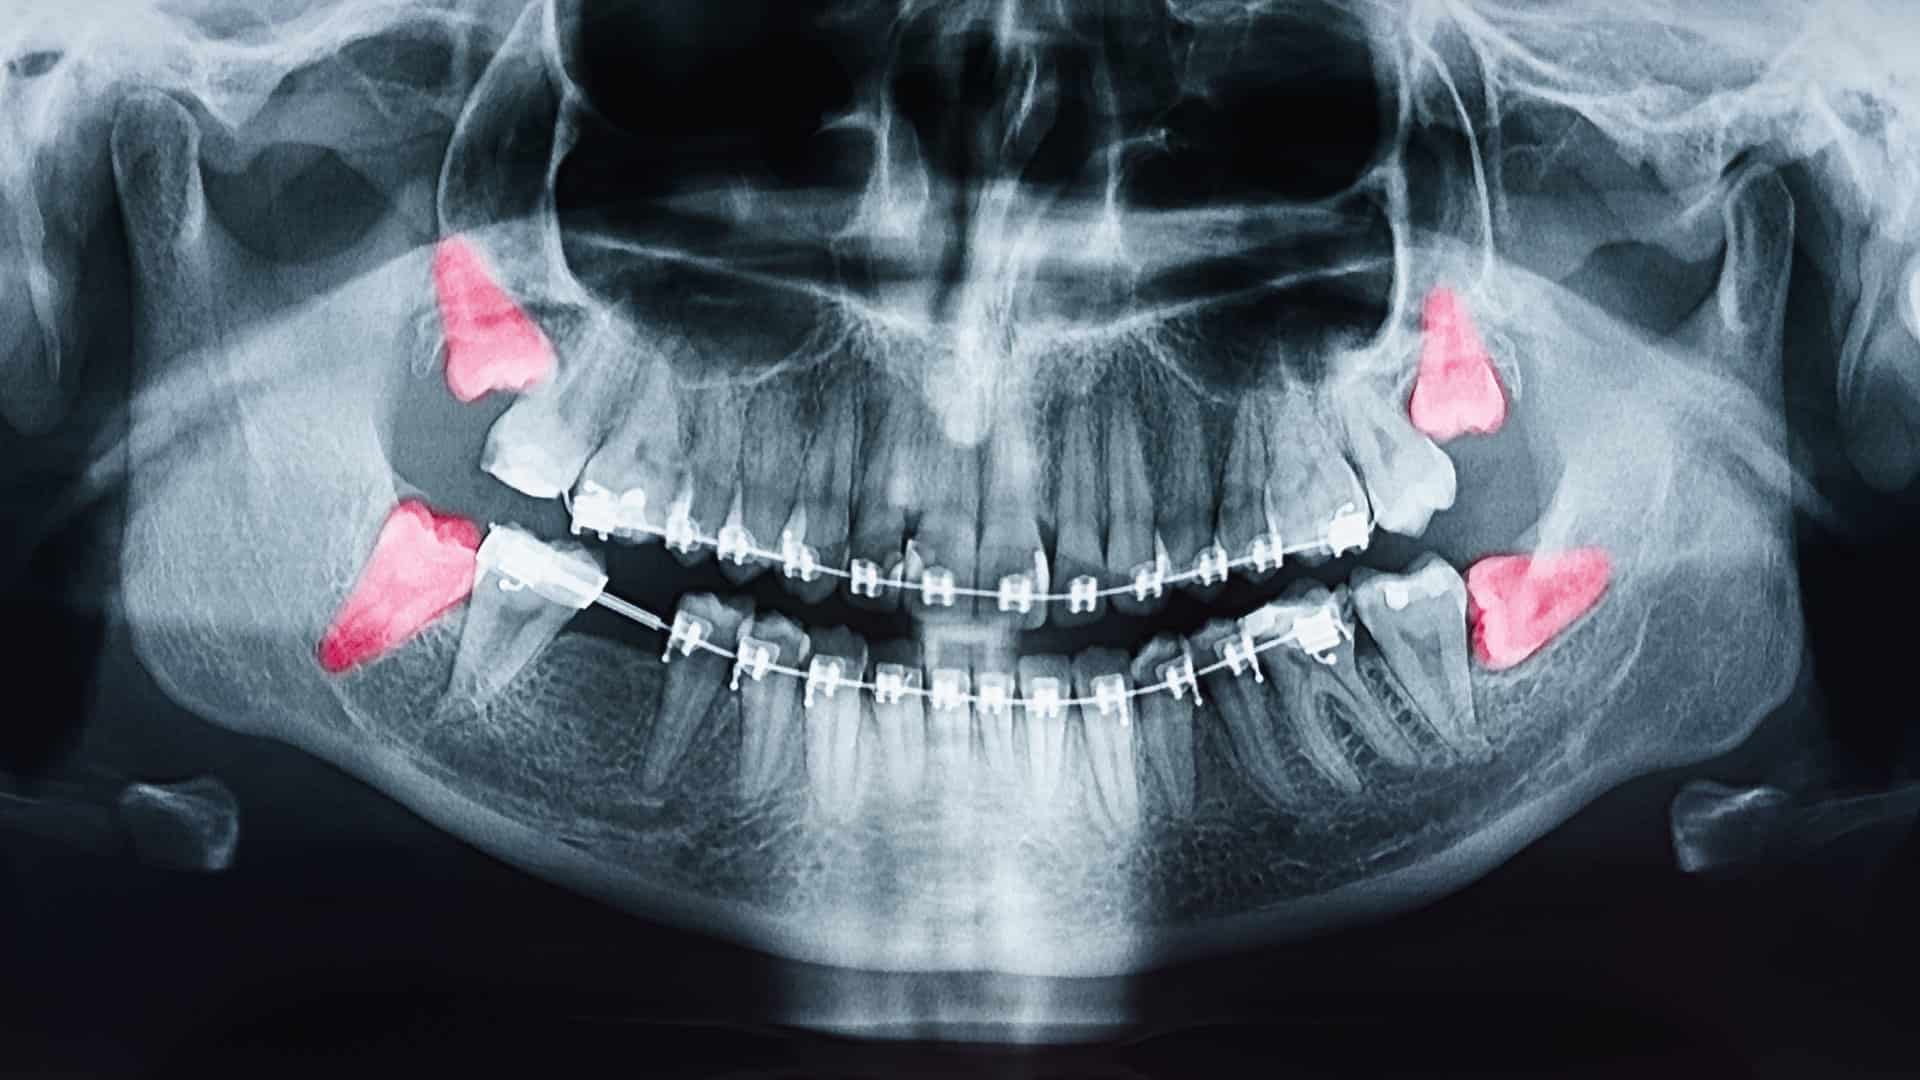

Required when the tooth cannot be removed through the usual method and a minor surgical approach is necessary. This commonly applies to impacted wisdom teeth or teeth that are partially or fully covered by gum and bone.

After the area is fully numbed, a small opening is made in the gum and a small amount of bone may be removed if needed. The tooth is sometimes divided into sections to allow for safe removal. Stitches are placed at the end of the procedure, and the healing period may take slightly longer.

Required when the tooth cannot be removed through the usual method and a minor surgical approach is necessary. This commonly applies to impacted wisdom teeth or teeth that are partially or fully covered by gum and bone.

After the area is fully numbed, a small opening is made in the gum and a small amount of bone may be removed if needed. The tooth is sometimes divided into sections to allow for safe removal. Stitches are placed at the end of the procedure, and the healing period may take slightly longer.

If your wisdom tooth has fully erupted and is positioned normally, it may be removed with a simple extraction under local anaesthesia. But if the tooth is impacted or partially erupted, a minor surgical procedure may be required. This involves gently opening the gum to access the tooth.

Ignoring problematic wisdom teeth can lead to infection, cyst formation, gum disease, and crowding of nearby teeth. Our dentists can help you assess your wisdom tooth early with X-rays to manage the issue before it becomes more serious or more uncomfortable.